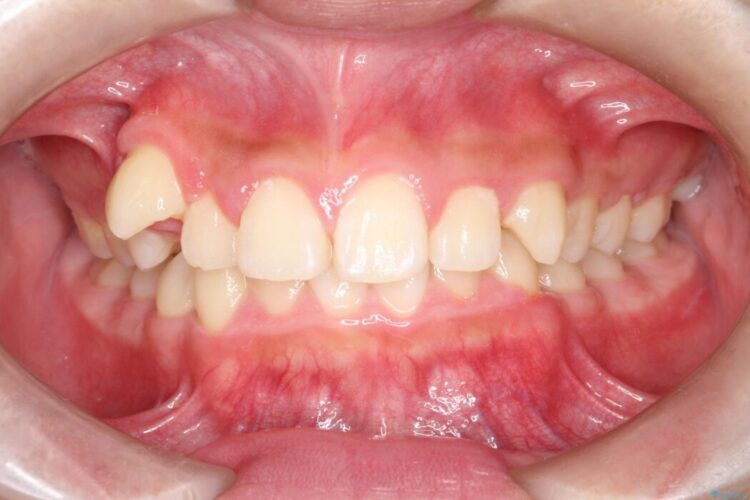

破折したセラミックインレーのやり替え

他院で装着されたセラミックインレー(MOD窩洞)が破折したとご来院されました。

治療期間(治療回数):1ヶ月(2~5回) | 概算治療費:15.4万円(税込)(オールセラミッククラウン14.3万円+仮歯1.1万円)